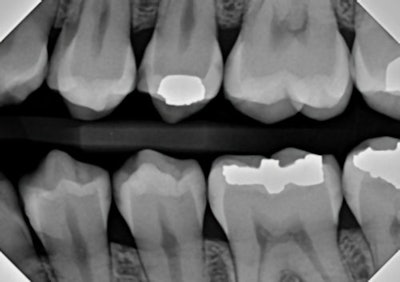

Figure 4: Traditional bitewing radiography indicates clear decay on tooth #13, with some evidence of incipient lesions on #s 12, 14, 18, 19, 20, and 21. It is quite possible for me to miss one or more of these lesions on the lower teeth during busy times at the office.Figure 4: Traditional bitewing radiography indicates clear decay on tooth #13, with some evidence of incipient lesions on #s 12, 14, 18, 19, 20, and 21. It is quite possible for me to miss one or more of these lesions on the lower teeth during busy times at the office.

Figure 5: AI radiographic interpretation helps highlight lesions and provides insight as to the extent of the decay.Figure 5: AI radiographic interpretation helps highlight lesions and provides insight as to the extent of the decay.